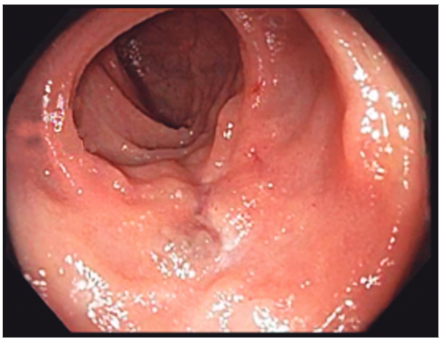

A los seis meses del tratamiento, intercurrió con un nuevo episodio de anemia sintomática. Se realizó enteroscopía anterógrada con doble balón (Fujinon® serie EN-450T5), sin evidencia de lesiones, con marcación del sitio de máxima inserción y enteroscopía retrógrada, evidenciandose en ileon, proximal a la cicatriz del tratamiento previo (Figura 2) una lesión similar a la anterior (Figura 3), de 25 mm de diámetro. Se realizó escleroterapia con polidocanol al 1% (seis mililitros), sin complicaciones.

Figura 2. Área deprimida de aspecto cicatrizal, que se evidencia por endoscopia y corresponde a

escleroterapia de hemangioma de ID.